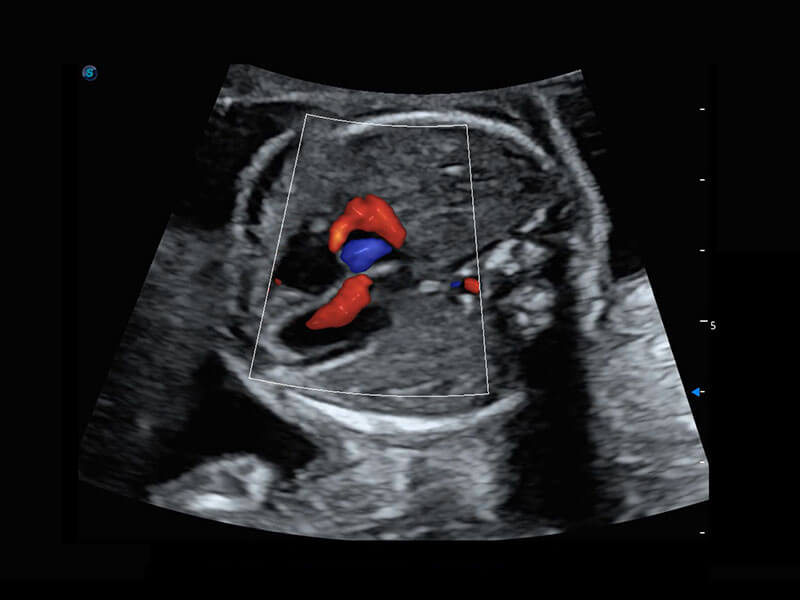

早孕筛查

P60在胎儿早孕期超声筛查中为您带来优异的图像质量。

• 早孕-胎心

• 高分辨率容积成像-早孕胎儿

• 胎儿体循环

• 光影成像-孕囊